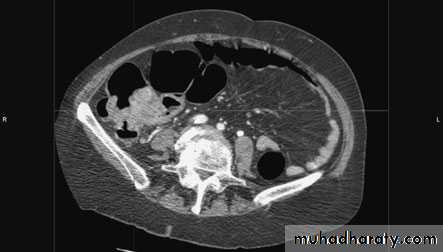

RadiologyDouble-contrast barium enema is used when colonoscopy is contraindicated.it shows a cancer of the colon as a constant irregular filling defect.Ultrasonography is often used as a screening investigation forliver metastases over the size of 1.5 cm, and CT is used in patientswith large palpable abdominal masses, to determine local invasion,and is particularly used in the pelvis in the assessment ofrectal cancer.

there has been the introduction of virtual colonoscopy, which is effective in picking up polyps down to size of 6 mm. This mayeven replace colonoscopy as the standard investigation in thefuture. Urograms have a role in left-sided tumours where there is evidence of hydronephrosis on CT or ultrasound.